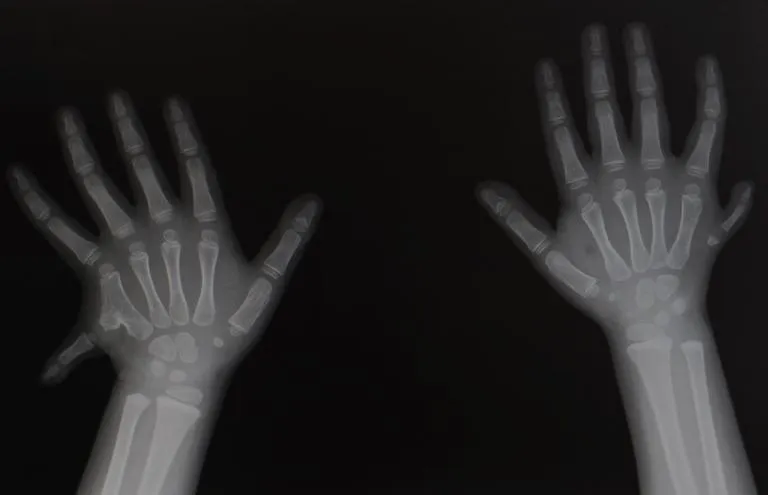

Polydactyly is a condition where a person is born with more than the usual number of fingers or toes. Polydactyly, also known as hyperdactyly, is a medical condition characterized by the presence of extra fingers or toes. The term “polydactyly” comes from the Greek words “polys,” meaning “many,” and “daktylos,” meaning "digits". Polydactyly is one of the most common birth defects affecting babies’ hands and feet1. It can occur in various forms, with the extra digit being fully formed and functional, partially formed with some bone, or just a small mass of soft tissue2. The extra digit often grows next to the fifth finger or toe. There are several types of polydactylies, classified by the position of the extra digit:

Preaxial (radial/tibial) polydactyly: An extra thumb or big toe.

Central polydactyly: An extra finger or toe near the middle digits.

Postaxial (ulnar/fibular) polydactyly: An extra pinkie finger or toe.